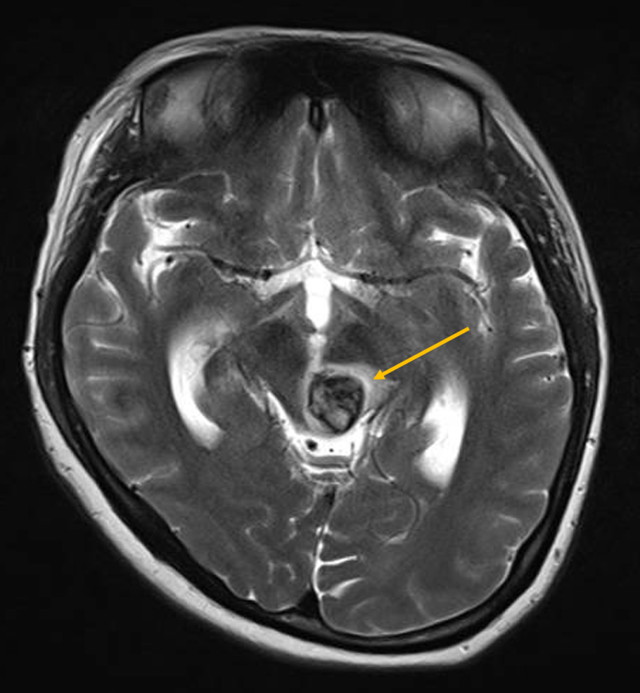

Kết quả chụp MRI cho thấy khối dị dạng mạch máu dạng hang rất hiếm gặp ở người bệnh.

Đó là trường hợp sản phụ Nguyễn Ngọc H. (30 tuổi, ngụ tại TP.HCM) được chuyển đến cấp cứu tại BV ĐHYD TP.HCM trong tình trạng hôn mê, mất ý thức. Thời điểm nhập viện, chị H. đang mang thai ở tuần thứ 34, trong lúc dùng bữa tối thì đột nhiên méo và tê mặt, nuốt sặc, yếu liệt nửa người rồi hôn mê sâu.Tại khoa Cấp cứu BV ĐHYD TP.HCM, sau khi tiến hành cấp cứu và thực hiện các xét nghiệm cần thiết, các bác sĩ đã hội chẩn và cho biết sản phụ bị xuất huyết giai đoạn cấp ở mặt sau bán phần trái cuống não, dẫn đến đột quỵ.Theo ThS BS. Đặng Lê Phương – Khoa Ngoại Thần kinh BV ĐHYD TP.HCM, đây là tình trạng dị dạng mạch máu dạng hang rất hiếm gặp, phần thân não của sản phụ bị tổn hại, xuất huyết nặng dẫn đến hôn mê, ảnh hưởng lớn đến hệ hô hấp và tuần hoàn. Trường hợp này vô cùng nguy hiểm, có nguy cơ tử vong cao nếu không được cấp cứu và điều trị kịp thời. Bên cạnh đó, vì đường dẫn truyền cảm giác và vận động đi ngang vùng thân não này, việc phẫu thuật cho người bệnh đòi hỏi kỹ thuật và sự cẩn trọng cao vì có nguy cơ bị liệt hoặc mất cảm giác sau mổ. Quá trình thực hiện cấp cứu và điều trị cho sản phụ vô cùng căng thẳng và gấp rút. Tại phòng Cấp cứu, sản phụ được đặt nội khí quản, tiến hành thở máy và chụp CT não bộ. Sau khi hội chẩn liên chuyên khoa xác định tình trạng sản phụ có thể diễn tiến nặng bất cứ lúc nào, các bác sĩ quyết định mổ lấy thai để cứu con trước.